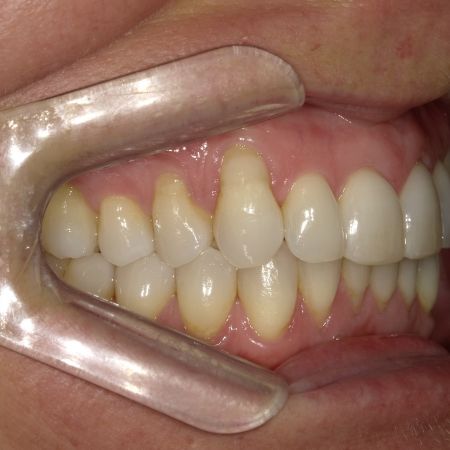

Während der Behandlung